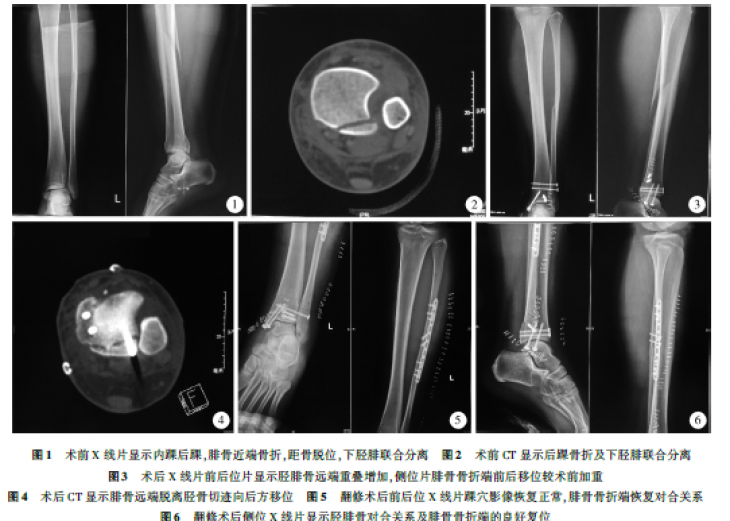

Maisonneuve损伤因涉及下胫腓联合韧带的损伤及腓骨近端骨折,易造成踝关节对合关系及稳定性改变,往往需要手术治疗,手术虽不复杂却存在严重失误的风险。本文通过总结1例Maisonneuve损伤手术治...